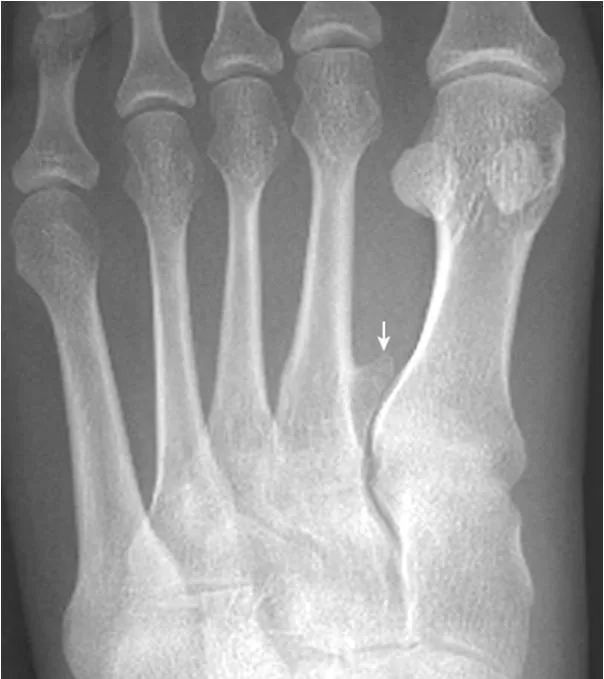

19.拇趾多分籽骨:

拇趾内外侧籽骨可表现为二分籽骨(箭)或三分籽骨(箭头),为正常变异,需与籽骨骨折、坏死鉴别。骨折边缘多不规则,坏死密度多不均。